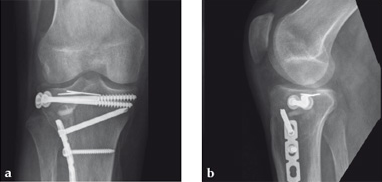

Case 2: A 38-year-old man sustained a lateral tibia plateau fracture (Müller AO Classification 41-B.3/Schatzker type II).

(Case provided by Michiel Verhofstad, Tilburg, The Netherlands)

After opening the lateral wedge, the osteochondral fragment was reduced and maintained with two K-wires. A gap beneath this fragment was left. Subsequently, a 3.2 mm hole was drilled in the lateral wedge using an inside-out technique. Then the lateral fragment was reduced. A 3-hole buttress plate, followed by two subchondral compression screws were used for final fracture fixation. Finally, Norian drillable was injected in the gap through the predrilled hole. Weight bearing was started after 6 weeks. At 6 months the fracture had healed anatomically and the patient was complaint-free.